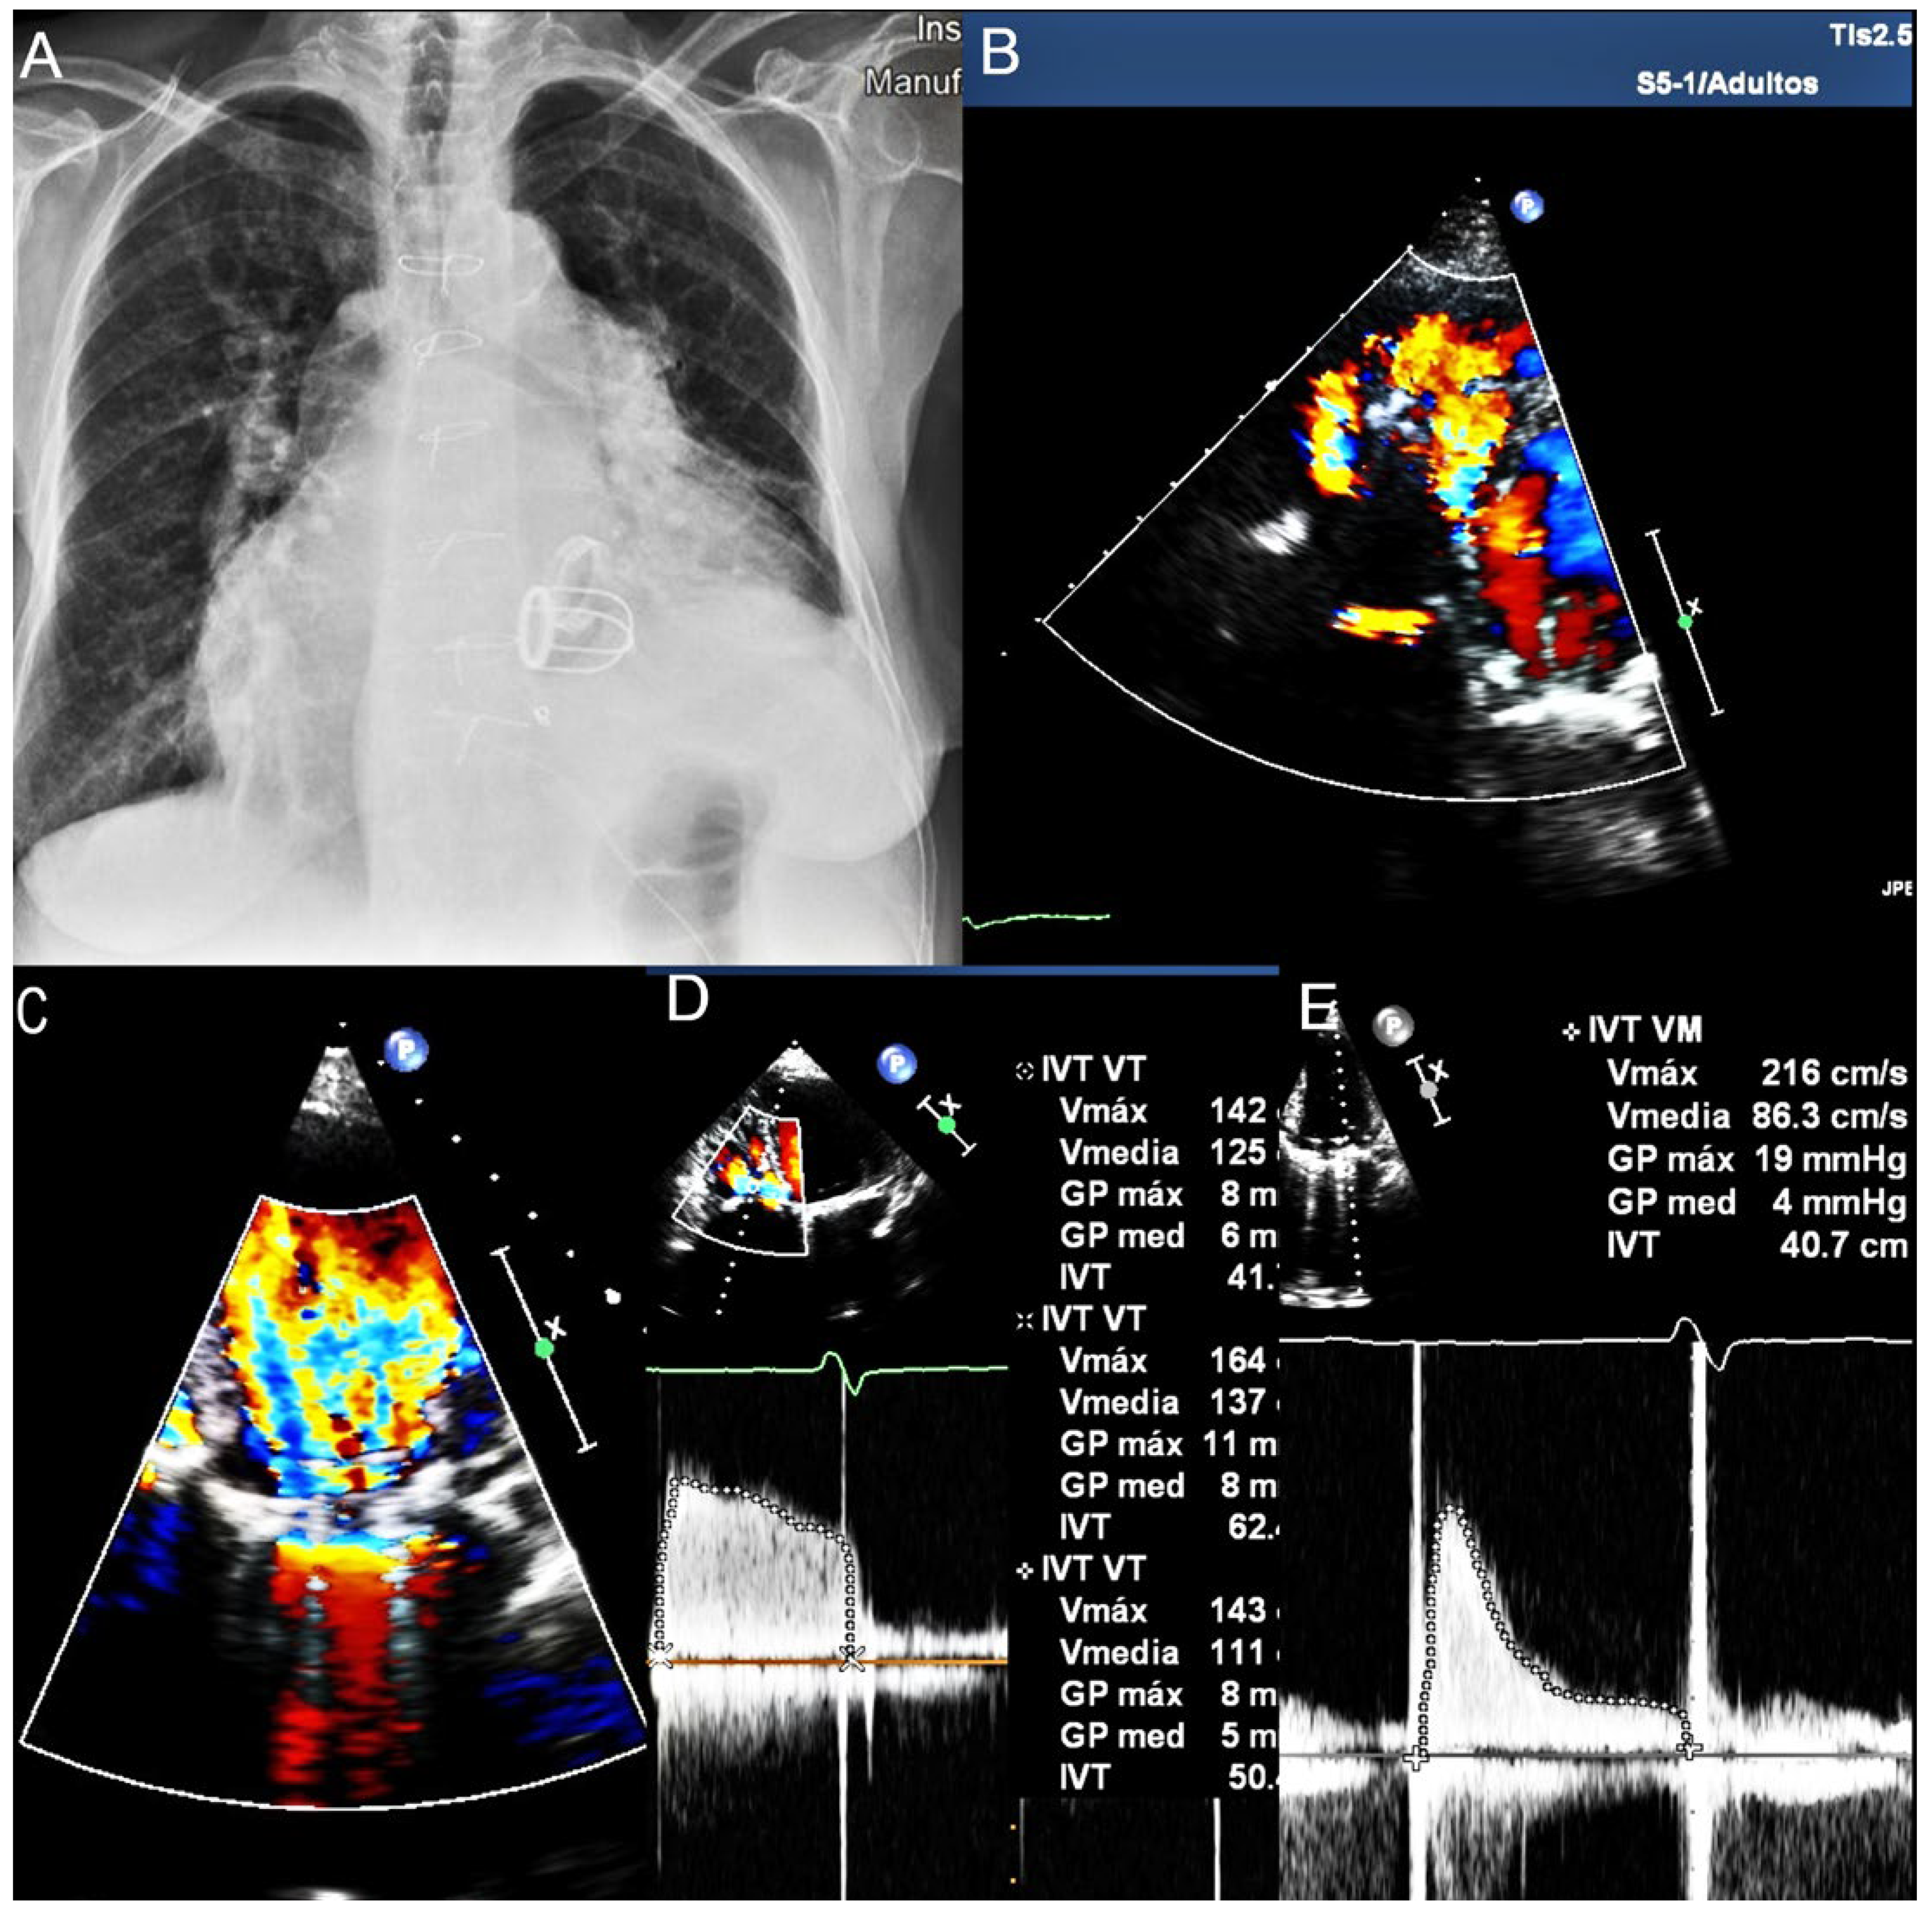

A Forgotten Prosthesis in a Forgotten Valve: A Surprising Case Report

Case